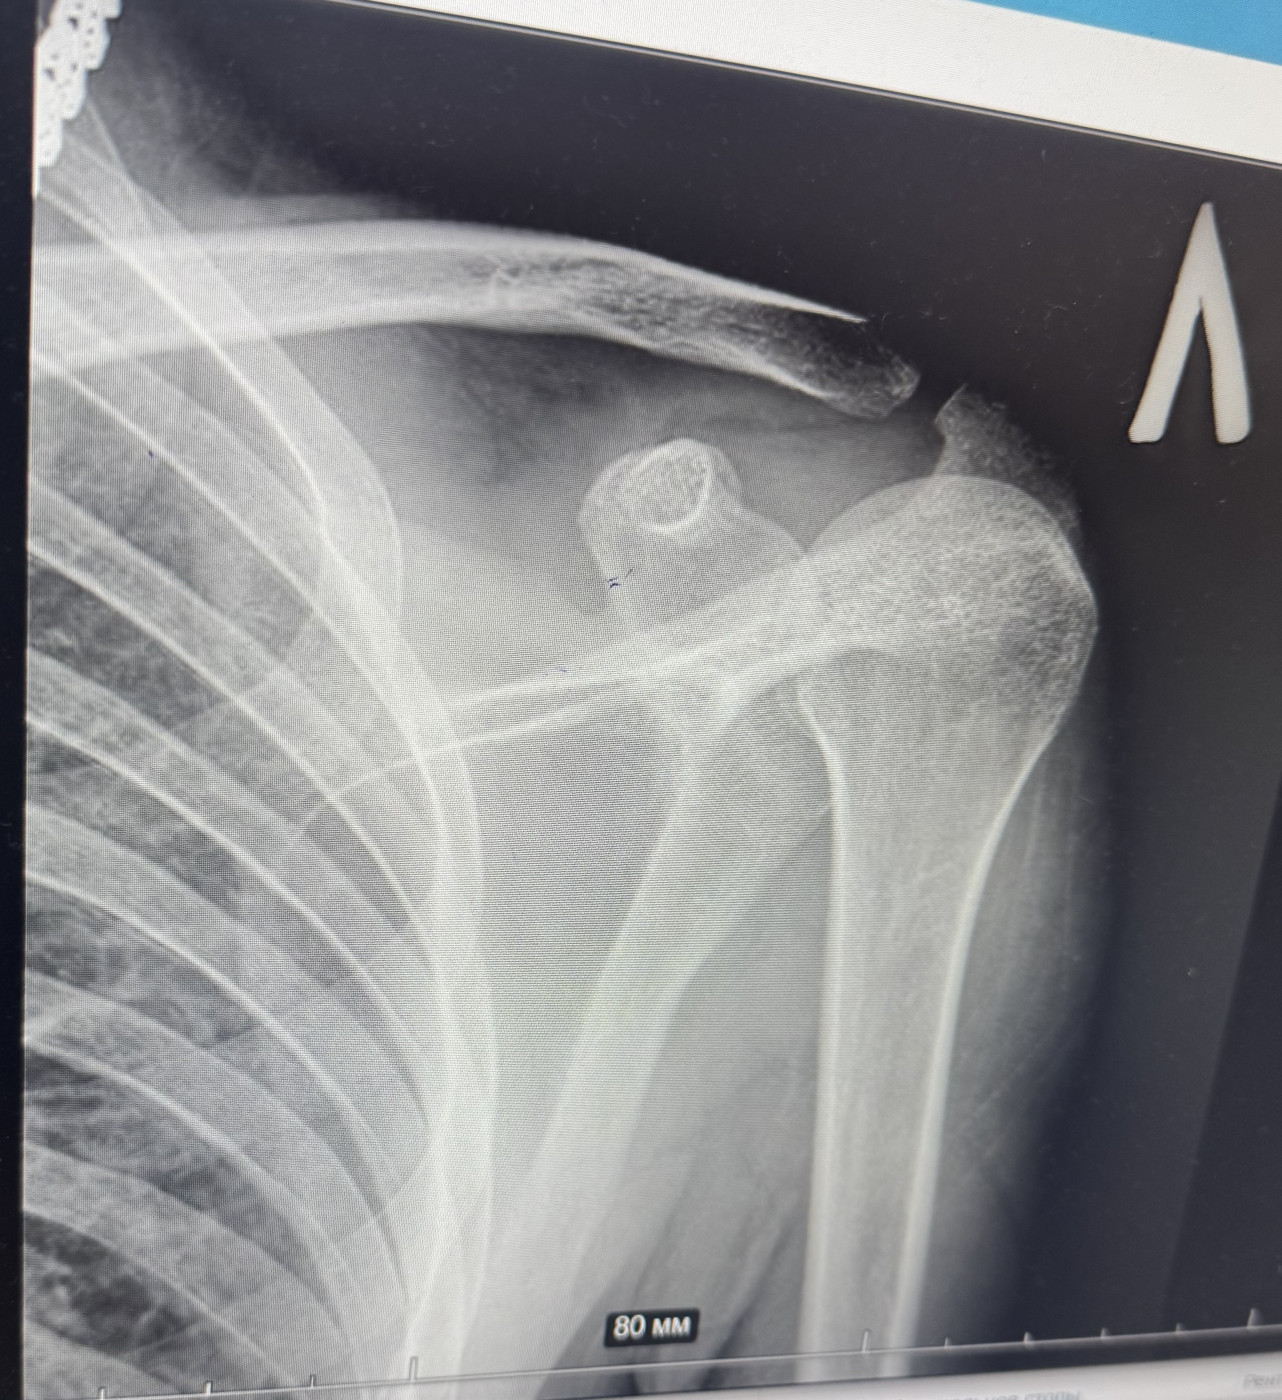

Перелом бедра